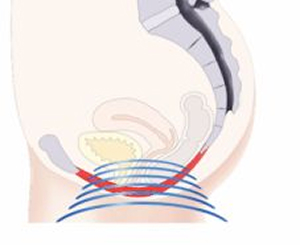

TRƯỚC

Các cơ sàn chậu không đủ khả năng hỗ trợ các cơ quan vùng chậu và ảnh hưởng đến khả năng kiểm soát bàng quang.

ĐIỀU TRỊ

Bàn tập cơ sàn chậu kích thích hiệu quả các cơ sàn chậu với hàng ngàn con co thắt cơ mỗi lần điều trị.

SAU ĐIỀU TRỊ

Kích thích làm khỏe cơ sàn chậu, giúp lấy lại khả năng kiểm soát các cơ sàn chậu và bàng quang.